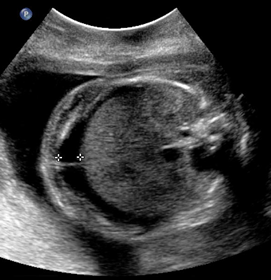

Above. Case 1. 24 3/7 weeks gestation. Sacrococcygeal teratoma. Longitudinal scan of lower spine showing sacrum with associated mixed cystic and solid mass.

Above. Case 1. 24 3/7 weeks gestation. Sacrococcygeal teratoma. An oblique scan through the same area shows both solid and cystic areas as well as calcifications, which are commonly seen in teratomas. The mass appeared completely external.

Above. Case 1. 24 3/7 weeks gestation. Sacrococcygeal teratoma. Similar part of the tumor as above showing cysts of various sizes.

Above. Case 1. 24 3/7 weeks gestation. Sacrococcygeal teratoma. The predominant cyst is large and contains anechoic fluid. No polyhydramnios or evidence for fetal hydrops were noted. Delivery occurred at term. Uneventful resection and repair occurred on day 2 of life.